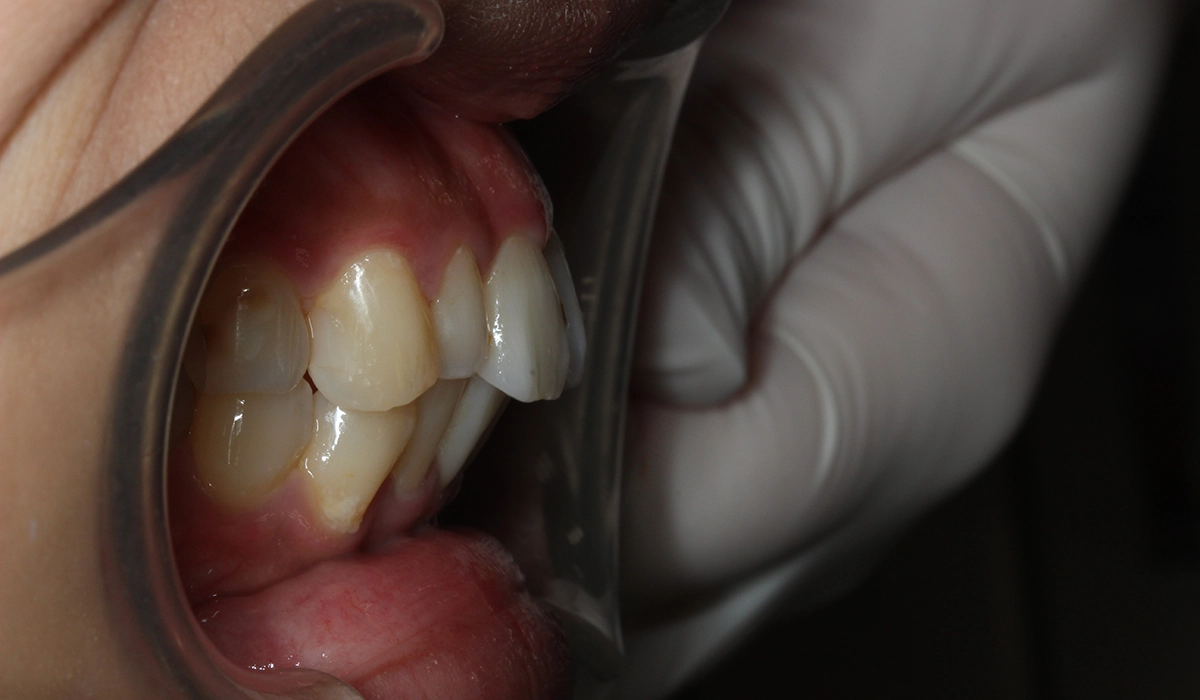

術前:右側

術後:右側